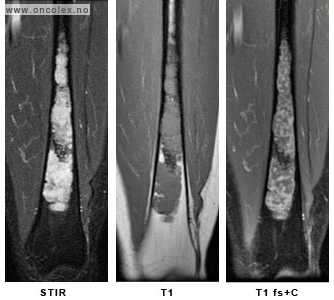

Moderne bildediagnostikk gir detaljert og pålitelig informasjon om svulstens karakter og utbredelse lokalt i knokkelen og vevet rundt. Dette er viktig for planleggingen av vevsprøve og behandling. Man trenger også bilder som viser andre deler av kroppen enn der svulsten sitter for å vite om det er tegn til spredning av svulsten til andre organer. De mest vanlige undersøkelsene som gjøres er CT og MR.

- MR er vesentlig for kartlegging av svulstens utbredelse og hvilke anatomiske strukturer den berører.

- CT viser skjelettets kalkholdige komponent og er bedre enn røntgen for fremstilling av bløtdeler. CT er også aktuelt dersom det foreligger forhold som taler i mot MR, for eksempel pacemaker.